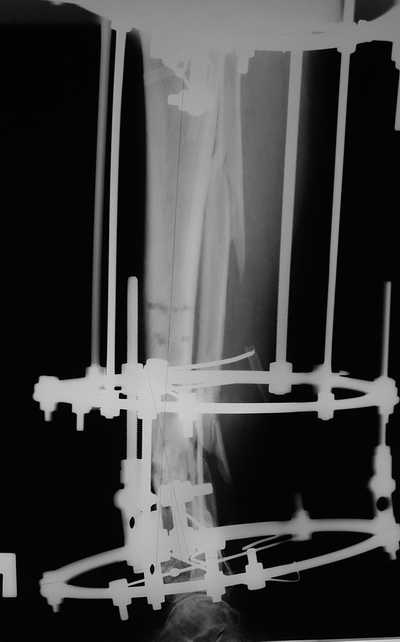

Еще один пример.

Мужчина, 33 года, резекция б\б кости по поводу остеомиелита после открытого перелома. Стандартная методика билокального остеосинтеза (рис 1 и 2). В конце удлинения выявилось неудовлетворительное взиморасположение перемещенного фрагмента и дистального отломка (рис 3). Планирование (рис 4).

Адаптация отломков гексаподом за 5 дней (рис 5). Замена гексапода на обычные штанги (рис 6 и 7)